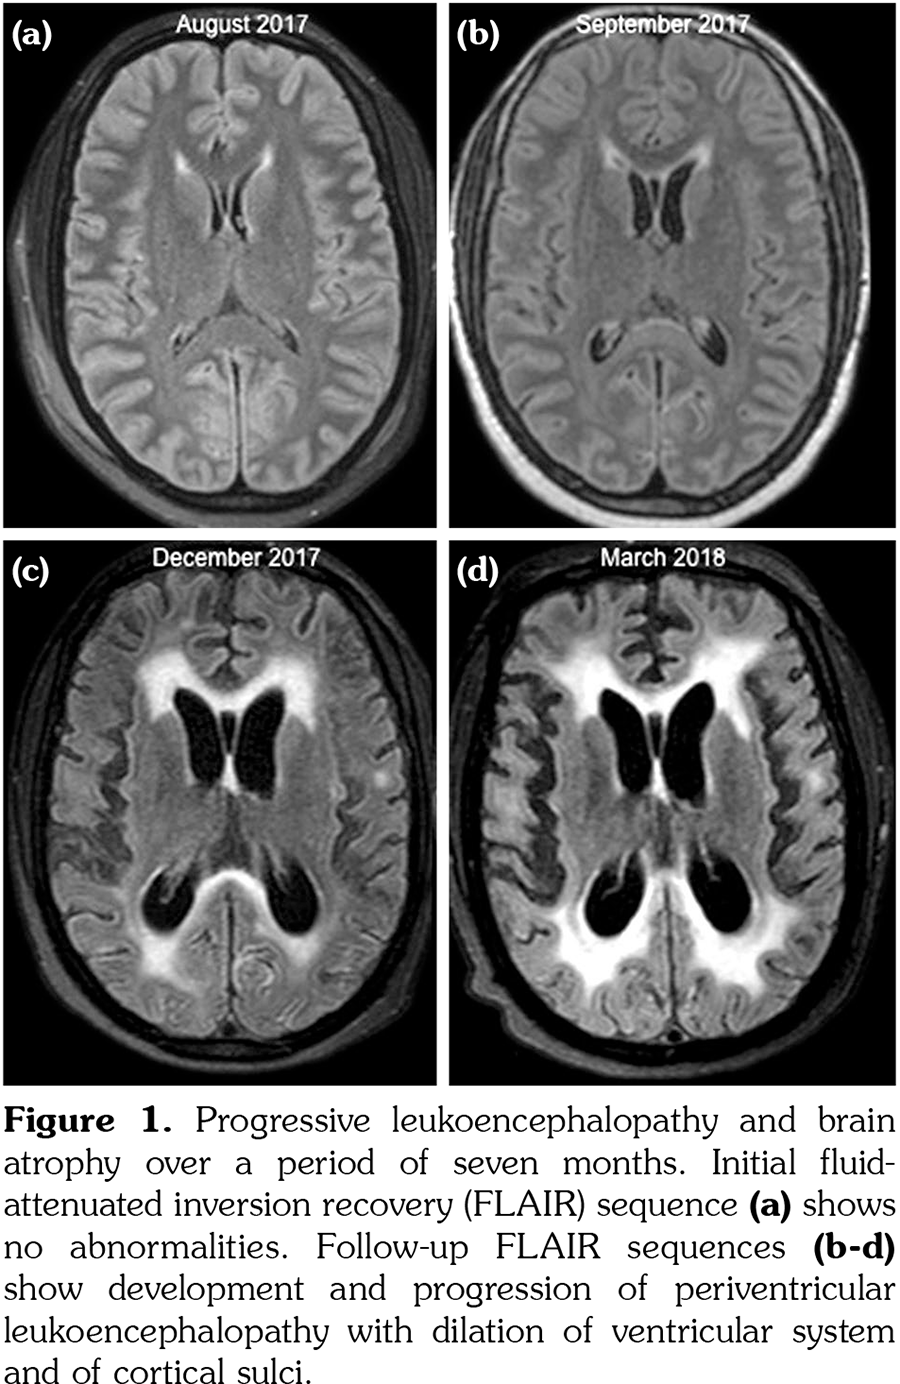

Initial brain MRI, using a standard protocol, was normal (Figures 1a and 2a). Due to rapid deterioration of the neurological status, a follow- up MRI was performed three weeks later (Figures 1b and 2b), including gadolinium administration and angiographic sequences. A mild periventricular nonspecific leukoencephalopathy and an incipient dilation of the supratentorial ventricles were observed. No abnormal contrast- enhancement was present. MRI angiography and venography showed permeability of the vessels. The patient continued to deteriorate, in a span of several weeks, despite initiating high-dose intravenous methylprednisolone. The clinical suspicion of vasculitis was raised and a third MRI was performed, at 3.5 months from the onset, with a specific protocol including vessel-wall three-dimensional (3D)-high-resolution pre- and post-contrast black-blood sequences. This MRI showed severe progression of the leukoencephalopathy, and associated atrophy with marked dilation of the ventricles and the subarachnoid spaces (Figures 1c and 2c). High-resolution vessel-wall sequences showed multiple arterial segments with concentric contrast enhancement of the wall, of proximal and distal distribution (Figure 3), compatible with vasculitis. A treatment with high-dose intravenous cyclophosphamide was started. Clinical follow- up revealed a progressive improvement of the drowsiness with eventually stabilized neurological status, but the cognitive deficit was already extremely impaired. The fourth MRI exam, at seven months from the clinical onset, showed even more severe atrophy (Figures 1d and 2d). A comparative of the hippocampal formation, crucial for the memory circuit, showed normal features on the first MRI (Figure 2e) and marked “knife blade” atrophy on the last study (Figure 2f). Concomitant diseases, including cerebrovascular and cardiovascular events, were ruled out.